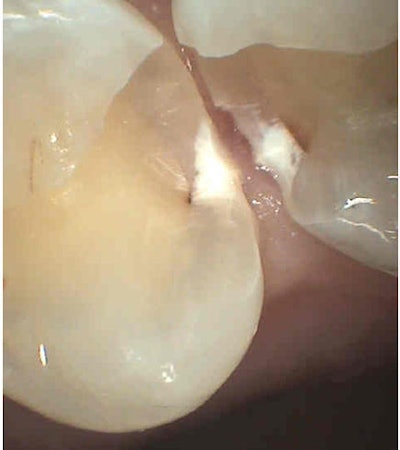

Now look at the caries clinically.

![]() |